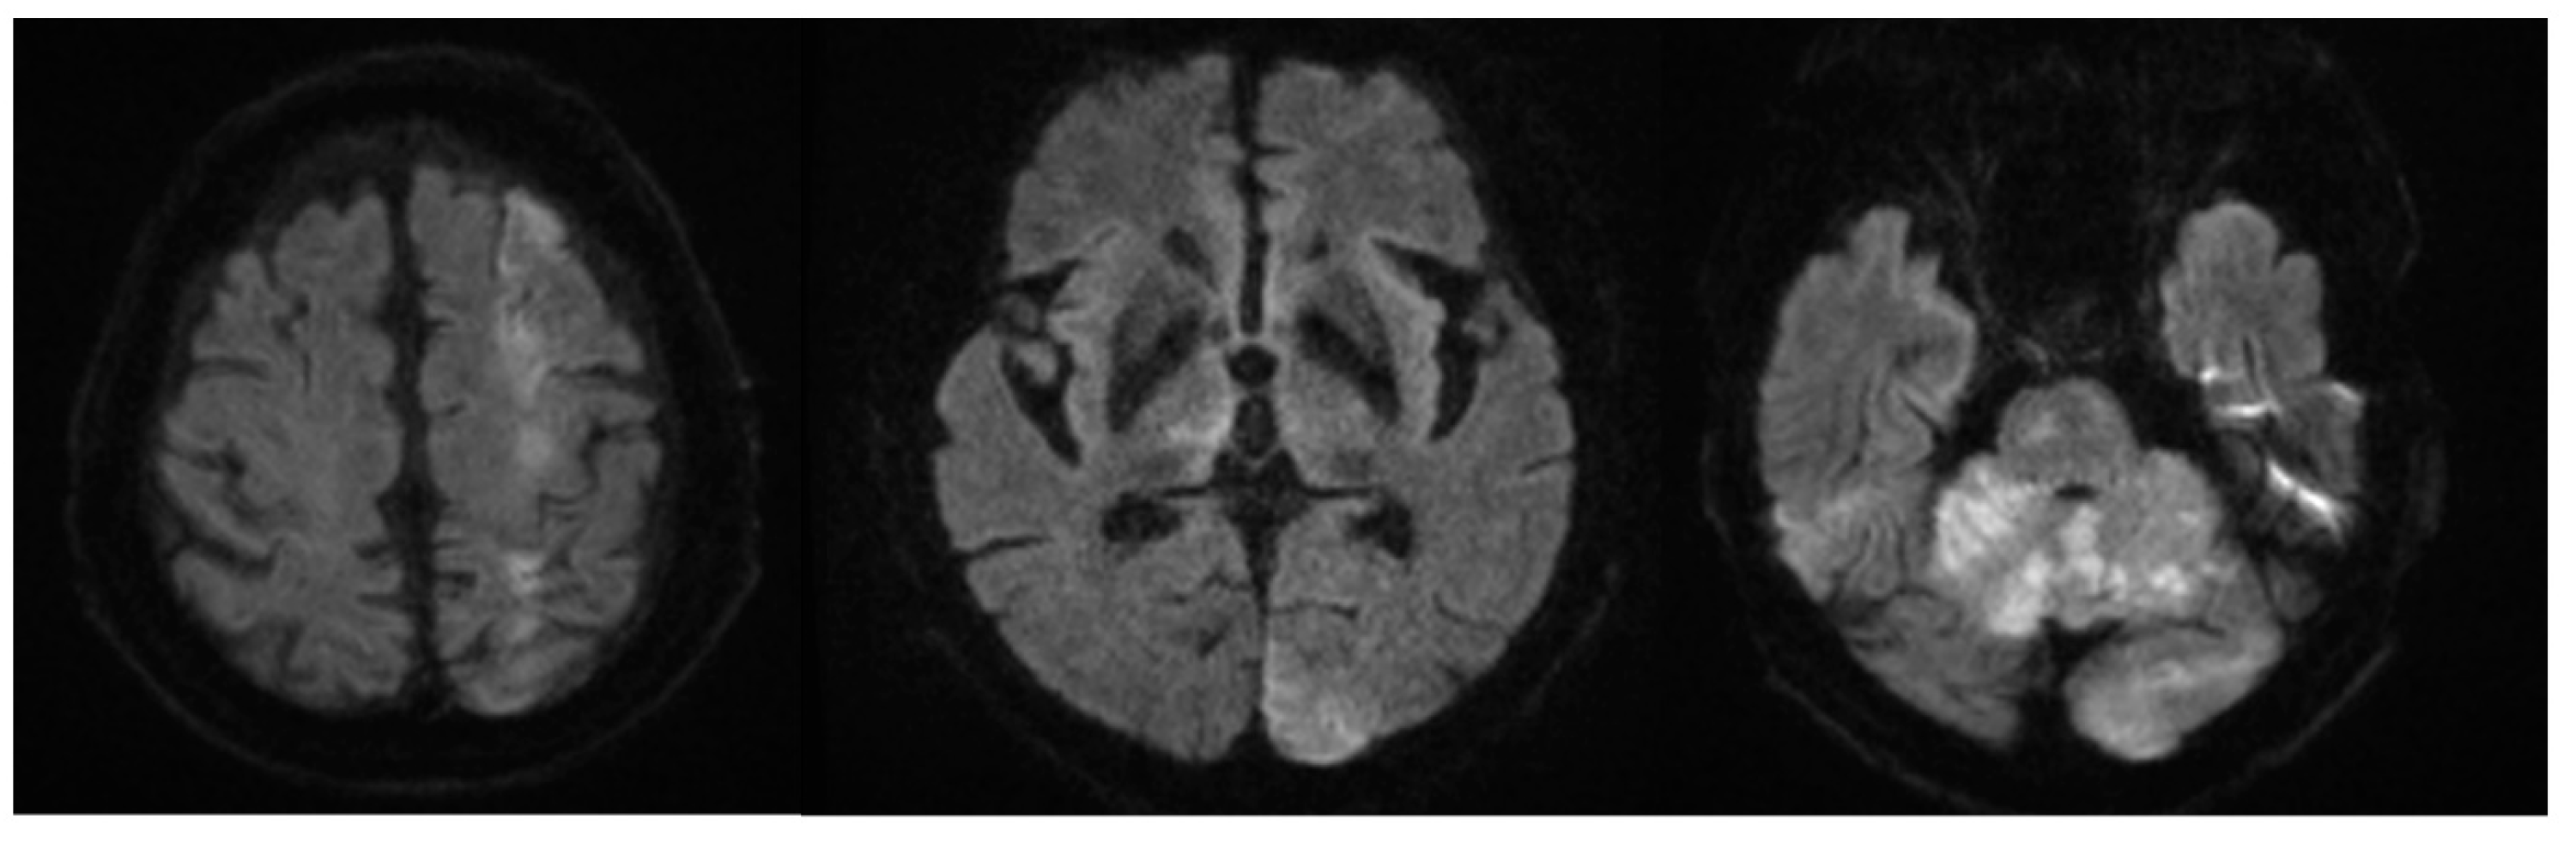

2. Case Description